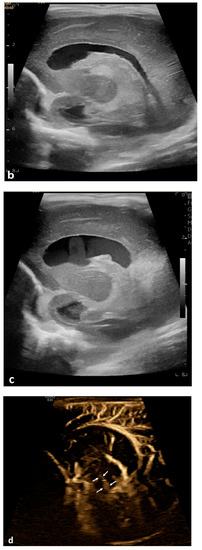

The evolving research on US systems has developed advanced Doppler technologies, such as MVI, that help depict flow in microvessels as well as in extravascular structures. Hwang and colleagues reported for the first time that CSF flow could be visualized in two neonates with a history of post-hemorrhagic hydrocephalus [8] (Figure 3). We found that using MVI, CSF flow could be identified in neonates and infants with different conditions, including hydrocephalus, IVH, or in some brains without apparent hydrocephalus or bleeding. Furthermore, there was a significant association between CSF flow visualization and an underlying diagnosis of IVH, either in the presence or absence of hydrocephalus.

Figure 3.

Illustration of caudocranial cerebrospinal fluid (CSF) flow direction, circulating from the fourth ventricle, passing through the cerebral aqueduct into the third ventricle (arrows). CC, corpus callosum; CSF, cerebrospinal fluid; LV, lateral ventricle; 3rd, third ventricle; CA, cerebral aqueduct; 4th, fourth ventricle. Modified from Hwang et al. with permission.